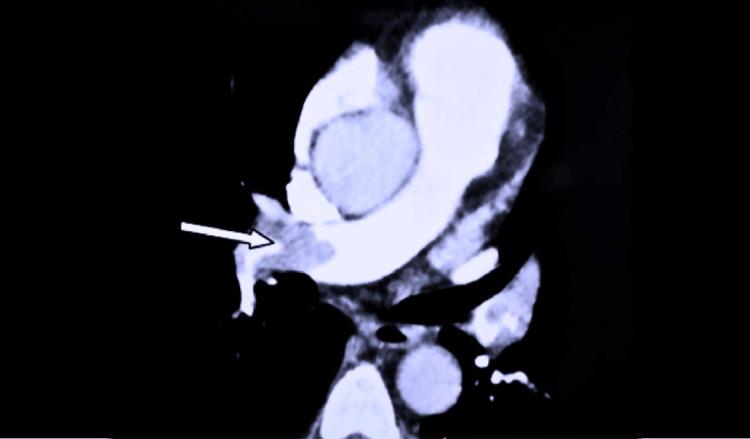

Acute pancreatitis is a disease characterized by local destruction of the pancreatic gland due to premature activation of pancreatic enzymes within the acinar cells. Tissue damage can activate an inflammatory cascade, which can lead to systemic complications. Although vascular complications are uncommon, they significantly contribute to mortality and morbidity. Pulmonary embolism being an exceptionally rare complication of acute pancreatitis is reported in only a few cases, and cases of pulmonary embolism without associated deep vein thrombosis in the lower limbs are extraordinarily rare and unreported in the literature. This article presents the case of a 22-year-old Sri Lankan woman diagnosed with severe acute pancreatitis. On the fifth day of her illness, she developed sudden-onset dyspnea, and imaging revealed a large pulmonary artery embolism affecting the right pulmonary artery and segmental branches in the right lower lobe, with a normal venous duplex scan of the lower limbs. We started her on anticoagulation and supportive care for her acute severe pancreatitis. Her dyspnea and pancreatitis improved with time. She was later diagnosed as heterozygous for the serine peptidase inhibitor Kazal type 1 (SPINK 1) mutation.

急性胰腺炎是一种由于腺泡细胞内胰酶过早激活导致胰腺局部破坏的疾病。组织损伤可激活炎症级联反应,进而导致全身并发症。尽管血管并发症并不常见,但它们对死亡率和发病率有显著影响。肺栓塞是急性胰腺炎极其罕见的并发症,仅有少数病例报道,而无下肢相关深静脉血栓形成的肺栓塞病例极为罕见,文献中未见报道。本文介绍了一名22岁斯里兰卡女性被诊断为重症急性胰腺炎的病例。在患病的第五天,她突然出现呼吸困难,影像学检查显示右肺动脉及右下叶节段性分支有一大块肺动脉栓塞,下肢静脉双功超声扫描正常。我们开始对她进行抗凝治疗并对其急性重症胰腺炎进行支持治疗。随着时间推移,她的呼吸困难和胰腺炎症状有所改善。她后来被诊断为丝氨酸蛋白酶抑制剂Kazal 1型(SPINK 1)突变的杂合子。